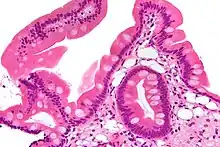

Endoscopy of the duodenum and jejunum can reveal pale yellow shaggy mucosa with erythematous eroded patches in patients with classic intestinal Whipple's disease, and small bowel X-rays may show some thickened folds. Other pathological findings may include enlarged mesenteric lymph nodes, hypercellularity of lamina propria with "foamy macrophages", and a concurrent decreased number of lymphocytes and plasma cells, per high power field view of the biopsy.

Diagnosis is made by biopsy, usually by duodenal endoscopy, which reveals PAS-positive macrophages in the lamina propria containing nonacid-fast, Gram-positive bacilli.[4][lower-alpha 1] Immunohistochemical staining for antibodies against T. whipplei has been used to detect the organism in a variety of tissues, and a polymerase chain reaction-based assay is also available,[4] which can be confirmatory if performed on blood, vitreous fluid, synovial fluid, heart valves, or cerebrospinal fluid.[10] PCR of saliva, gastric or intestinal fluid, and stool specimens is highly sensitive, but not specific enough, indicating that healthy individuals can also harbor the causative bacterium without the manifestation of Whipple's disease, but that a negative PCR is most likely indicative of a healthy individual.[4]